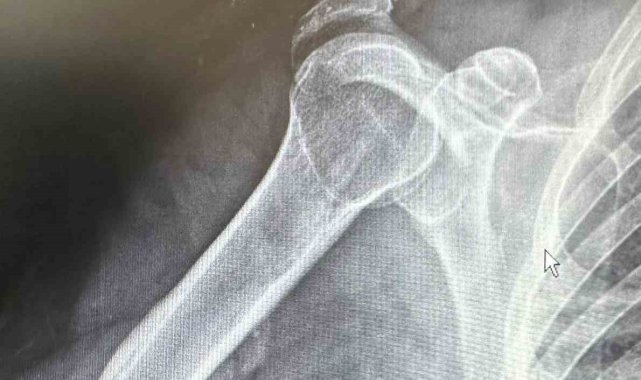

Dr. Başer, hastanın 64 yaşında omuz çıkığı nedeniyle kendilerine başvurduğunu söyledi. Kendisi, arkadaşlarıyla tenis oynarken omuz üzerine düşme sonrası omuzunda bir çıkık geliştiğini belirten Başer, "Normalde bu omuz çıkığını genç hasta grubunda görebiliyoruz. Hastamız ileri yaş olmasına rağmen aktif spor yapan bir hastamız. Bize başvurduğunda omuz eklemi yerinde değildi. Hastanın kemik yapısına tam uyumlu, nadir kullanılan özel bir plak ile başarılı bir ameliyat gerçekleştirdik. Daha sonra biz de ameliyat kararı verdik. Ameliyatında daha çok gençlerde kullanılan nadir, özel şekilli, çengel bir plak kullandık. Daha sonra filmlerini de çekip kontrol ettikten sonra hastamızın ameliyatını başarılı bir şekilde tamamladık. Başarılı ameliyatın ardından hemen fizik tedavi sürecini başlattık. Hastamız bugünden itibaren yavaş yavaş omuz hareketlerini yapabilecek hale geldi. Kol askısından bir an önce kurtulacak ve hastamız en geç 2-3 haftaya kadar eski omuz hareketlerine ağrısız kavuşmasını bekliyoruz" dedi.

Daha önce başvurduğu doktorların ileri yaşı nedeniyle ameliyatın mümkün olmayacağını ve kendiliğinden iyileşmesi gerektiğini söylediklerini belirten Rençber ise, "Benim gibi emekli olan arkadaşlarımla tenis oynarken omuz üstüne düştüm. Düşmem münasebetiyle omuzdaki açılma çok büyüktü. Birkaç doktora gittim ve Bu ameliyatın mümkün olamayacağını, 25 yaşına kadar olan hastaları genelde ameliyat yaptıklarını söylediler. 'Yaşının ileri yaş grubunda olduğunuz için dokunmuyoruz. O kendi kendine iyileşir' dediler. Sonra da Doktor Mehmet Yavuz Bey'e geldim. Mehmet Yavuz Bey durumu inceledi. Dedi ki, 'yapabilirim.' Bunda inşallah sıkıntı yaşamasın dedi şimdi başarılı bir ameliyat oldum, çok memnun kaldım. Bayağı ilgilendi. Ameliyat sonrası en ufak bir sancı, bir sıkıntı görmedim ve yaşamadım. Ameliyat sonrası bile omuzum neredeyse eskisi gibi hareket edebiliyorum, kısıtlılığım ilk gün bile ciddi şekilde azaldı" şeklinde konuştu.